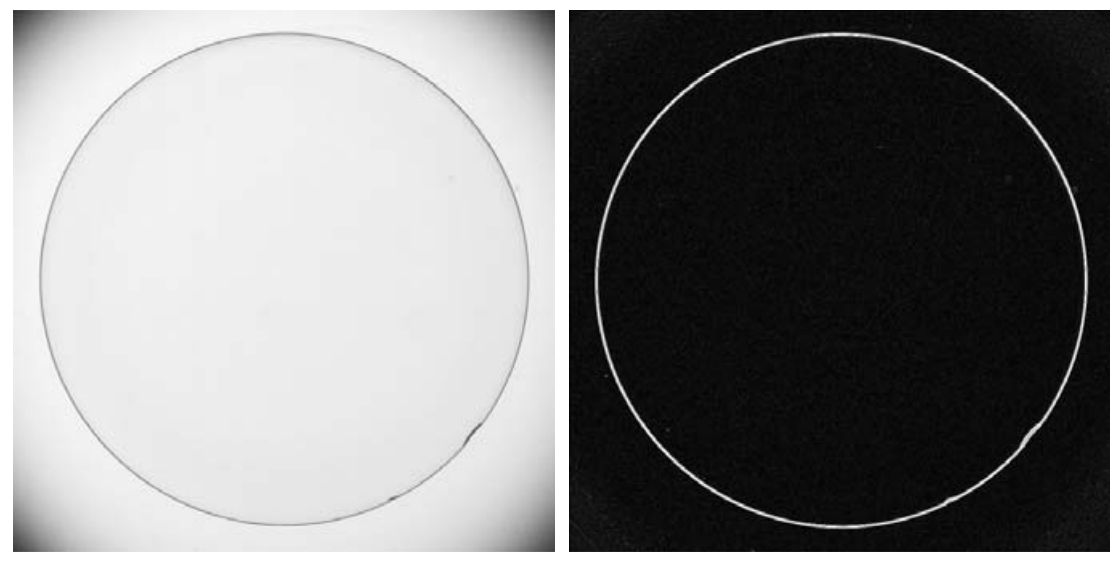

上图中是一张原始 X 光图片,右图为经过反转变换后的图片。